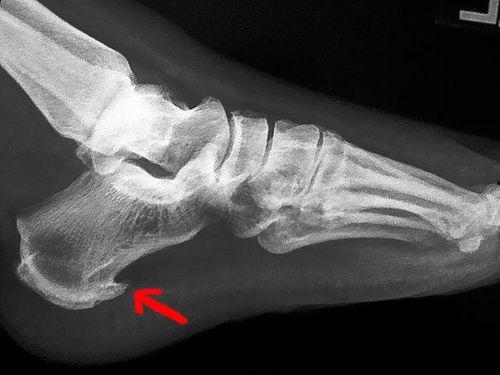

X光检查是骨头检查中最常见的方法之一。通过X光照射,医生可以清晰地看到骨骼的形态、密度和是否有骨折等情况。不过,X光检查有一定的辐射,所以不建议频繁进行。